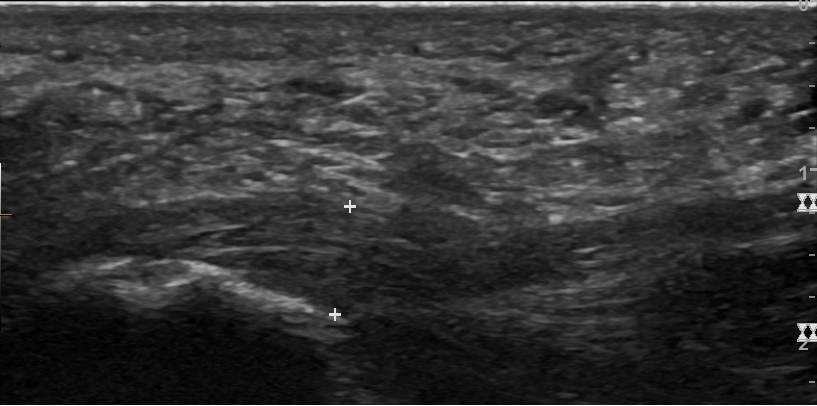

일반적으로 족저 근막염 진단을 위해 진단 영상 검사가 반드시 필요한 것은 아니다.[5] 하지만, 심한 발 통증의 다른 원인을 배제하기 위해 의사는 X-ray, 진단 초음파 또는 MRI 등의 영상 검사가 필요하다고 결정할 수 있다.

족저 근막염은 환자의 병력, 위험 요소, 임상 검사를 통해 의료 제공자가 진단한다.[1][14][15] 발바닥의 뒤꿈치 뼈 안쪽을 만져보면 압통이 느껴질 수 있다.[1][12] 장딴지 근육이나 아킬레스건이 뻣뻣하면 발의 등쪽 굽힘이 제한될 수 있다.[5] 발의 등쪽 굽힘은 족저 근막을 늘어나게 하여 통증을 유발할 수 있다.[1][36]일반적으로 족저 근막염 진단을 위해 X-ray, 진단 초음파, MRI 같은 영상 검사는 필요하지 않다.[5] 하지만, 발 통증의 다른 원인을 확인하기 위해 영상 검사가 필요할 수도 있다.

족저 근막은 세 개의 다발로 이루어져 있는데, 중앙 다발이 4mm로 가장 두껍고, 가쪽 다발은 2mm, 안쪽 다발은 1mm 미만이다.[17] 족저 근막의 두께가 두꺼워질수록 족저 근막염 발생 가능성이 높아진다. 초음파에서 4.5mm 이상, MRI에서 4mm 이상 두꺼워지면 진단에 도움이 된다.[18] 하지만 족저 근막 비후와 같은 다른 영상 소견은 족저 근막염 진단에 제한적인 유용성을 가진다.[13]

족저 근막염은 보통 환자의 병력, 위험 요소, 임상 검사 등을 종합하여 의료 제공자가 진단한다.[1][14][15] 발바닥의 뒤꿈치 뼈 안쪽을 만져보면 신체 검사 중 압통이 느껴질 수 있다.[1][12] 장딴지 근육이나 아킬레스건이 과도하게 뻣뻣하면 발의 등쪽 굽힘이 제한될 수 있다.[5] 이러한 움직임은 족저 근막을 늘어나게 하여 발의 등쪽 굽힘 시 통증을 유발할 수 있다.[1][36] 족저 근막염 진단을 위해 진단 영상 검사가 반드시 필요한 것은 아니다.[5] 하지만, 심한 발 통증의 다른 원인을 확인하기 위해 X-ray, 진단 초음파, MRI 등의 영상 검사가 필요하다고 판단될 수도 있다.